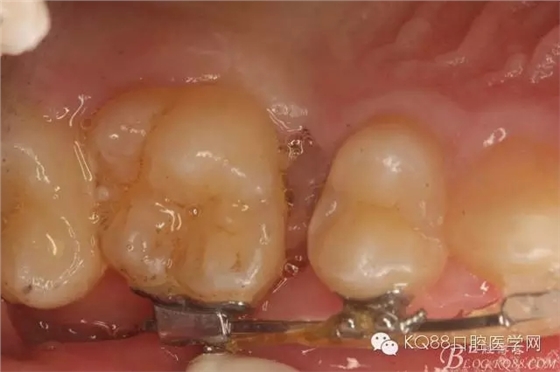

圖1.術前患者的口內(nèi)照片:16與14之間有約2mm間隙,矯治器已經(jīng)安裝到位。

圖2.從合面觀:16與14之間的牙間隙牙齦顏色異常,建議拍根尖片。